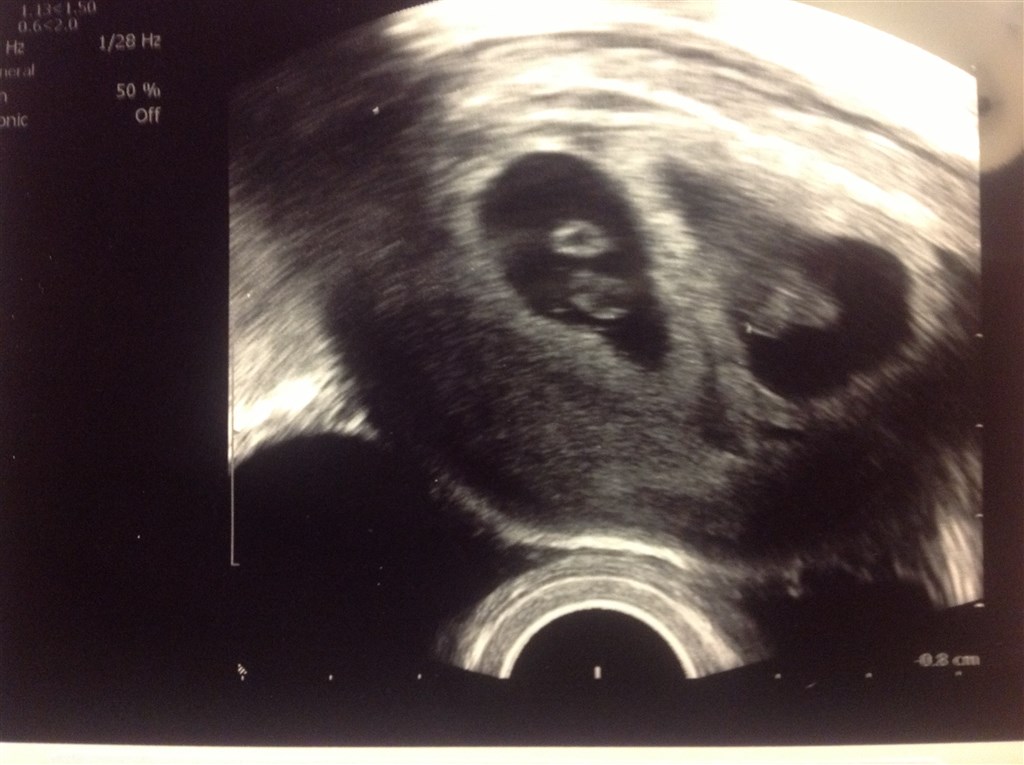

Vi havde en perfekt scanning.. De er 100% som de skal være de to krudt ugler..

Er 7+4 idag...